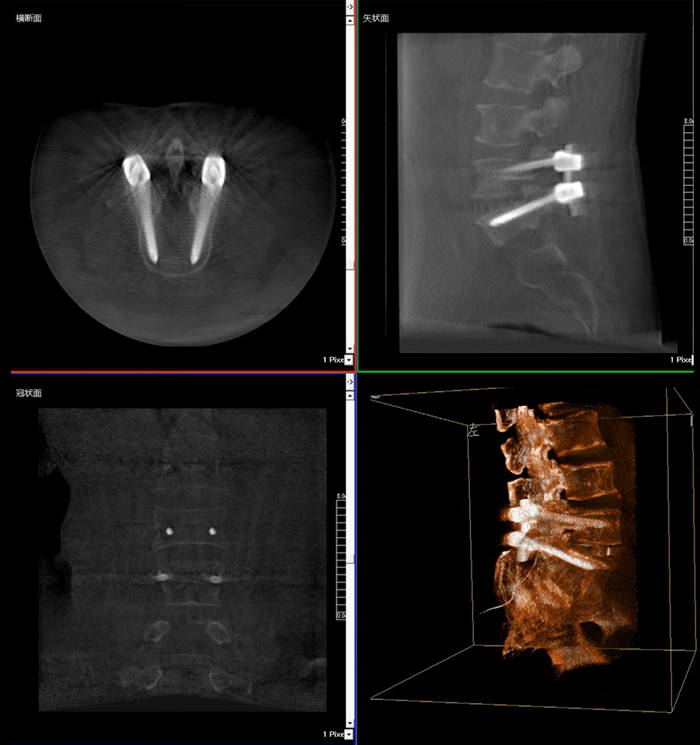

普愛(ài)醫(yī)療三維C臂X光機(jī)快速生成橫斷面、矢狀面、冠狀面斷層圖像和三維立體圖像,方便醫(yī)生確認(rèn)手術(shù)部位。三維C臂X光機(jī)的大平板帶來(lái)出色的顯示視野,可以更好的顯示手術(shù)部位全局情況,確保手術(shù)規(guī)劃及執(zhí)行的準(zhǔn)確性。

三維C臂X光機(jī)影像

普愛(ài)醫(yī)療三維C臂X光機(jī)二維、三維成像模式可快速切換,僅需30秒鐘,一鍵從二維切換至“術(shù)中CT”模式,完成術(shù)中三維圖像采集,同步生成“類CT”斷層圖像,方便醫(yī)生從各個(gè)角度各個(gè)層面來(lái)觀察病灶區(qū)域,準(zhǔn)確定位穿刺針位置。采用30CM*30CM的動(dòng)態(tài)平板探測(cè)器,成像范圍大(一次性可成像5節(jié)腰椎),無(wú)需反復(fù)透視,節(jié)約手術(shù)時(shí)間。